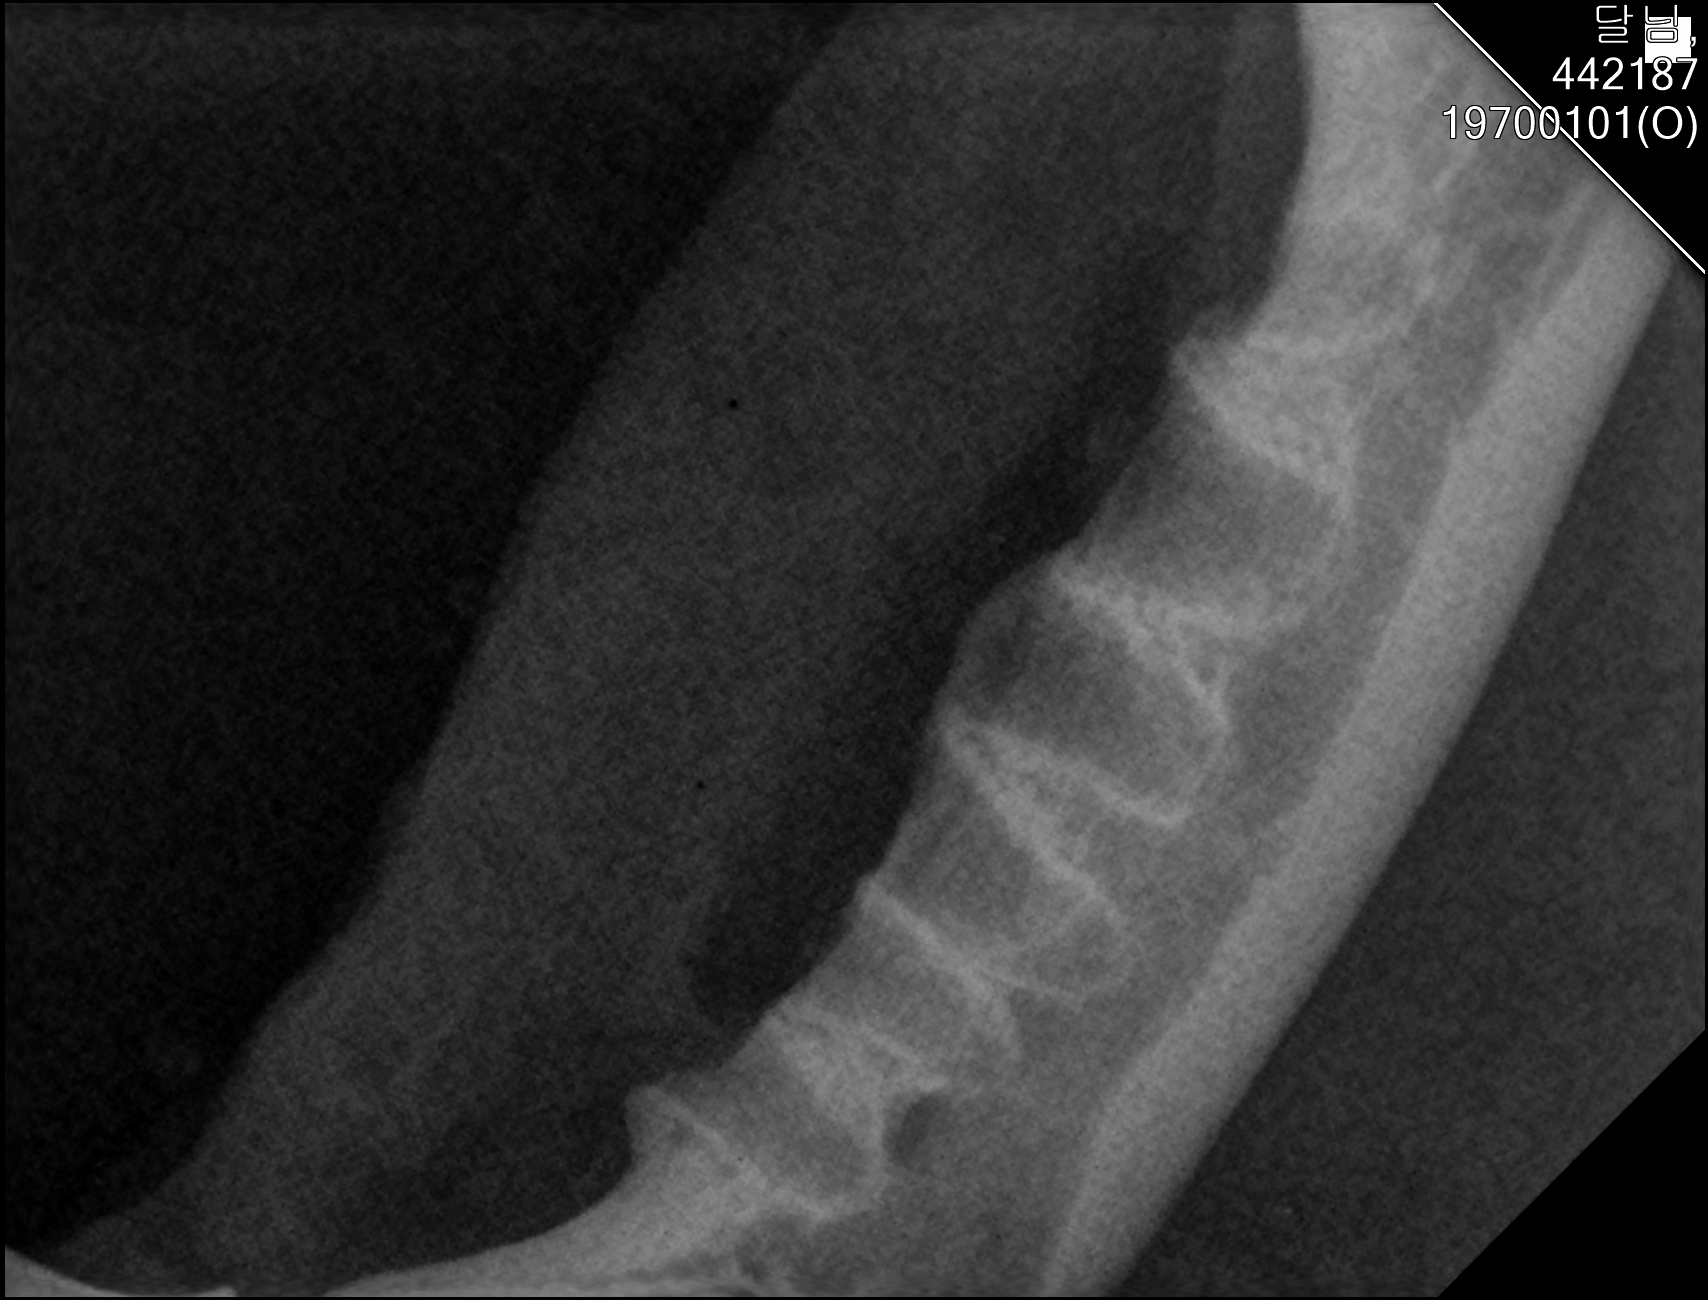

| 치료과정 | 달님이를 병원에 데려갔을때 거의 한달 가까이 먹질 못했기 때문에 몸무게는 2키로 초반대로 나갔고 마취하고 검사할수있는 상태가 아니였기 때문에 피검사를 통해서 간단히 검사후 입원하기 시작했습니다 탈수증세가 너무 심했고 수액을 맞으면서 자발식을 찾으려 했지만 달님이는 전혀 먹질 않았고 입원기간도 길어지게 되었습니다 그 와중에 청천벽력같은 소리를 듣게되었습니다 신장수치가 좋지않아 신부전이라는 결과였습니다 손도안타는 이아이를 제가 과연 케어할수있을까 너무 너무 걱정이였고 눈물이 앞을 가렸습니다 하지만 우선 체력을 회복한후 걱정은 나중에 하기로하고 달님이 치료에 집중하기 시작했습니다 병원에서도 선생님들이 달님이를 강제 급여도 해주고 수액도 계속 맞고 보니 꽉 막혀있던 코에서 콧물도 나고 소변도 보기 시작했습니다 그리고 다시 검사를 하고나니 다행히 신부전은 아니고 지방간이라고 하였습니다 아마도 오래전부터 먹는양이 줄어들었고 최근에 들어 아예 먹질못해서 간이 망가졌고 황달증세가 생겼다고합니다 어떤 이유에서인지모르겠지만 달님이는 원래 호흡기도 안좋았고 항상 콧물과 재채기를 달고산 아이라 호흡기도 안좋았고 이빨상태도 안좋아 밥을 못먹기 시작했던거같습니다 우선 체력회복이 중요하기때문에 집에서 케어한후 간 회복후 추후에 발치를 하기로 하였습니다 집에 온후 달님이는 바로 사료를 먹기시작했습니다 아마도 병원이 싫어서 밥을 안먹었던 모양입니다 매일 처방식과 약을 먹이면서 살을 찌우기 위해 이것저것 달님이가 좋아하는 캔과 츄르를 바치기 시작했고 다행히 달님이는 매일 맛있는 밥을 먹으며 살이 찌기시작했습니다 한달되는 날 발치와 검사를 위해 병원에 가서 검사를 하였는데 달님이는 3.86키로로 몸무게도 상당히 늘었으며 검사결과 모든 수치가 좋아졌습니다 그리고 마취후 이빨상태를 보니 치주염이 심각했고 이빨은 어금니부터 송곳니까지 다 내려앉은 상태였습니다 입안은 구내염이 시작되었고 원장님은 송곳니도 지금도 안좋지만 나중에 되면 더 아퍼질꺼라며 전발치를 해야한다 하였고 저는 달님이과 전발치를하고 길에서 잘 살수있을까 너무 걱정이였지만 나중에 아파서 또 구조후 마취하는것보다 낫다고 생각했고 밥자리도 잘 되어있어 전발치하고도 잘사는길냥이들 많다고 들어서 전발치를하게되었습니다 달님이는 수술을 잘 마쳤고 퇴원후 달님이는 집에서 10일정도는 약먹고 회복해야하기때문에 집에서 좀더 케어한후 방사할 예정입니다 |